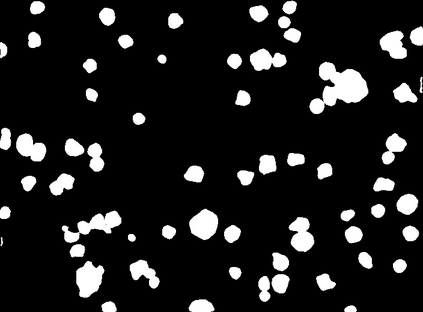

Bright-field microscopy, a cost-effective solution for live-cell culture, is often the only resource available, along with standard CPUs, for many low-budget labs. The inherent challenges of bright-field images -- their noisiness, low contrast, and dynamic morphology -- coupled with a lack of GPU resources and complex software interfaces, hinder the desired research output. This article presents a novel microscopy image analysis framework designed for low-budget labs equipped with a standard CPU desktop. The Python-based program enables cytometric analysis of live, unstained cells in culture through an advanced computer vision and machine learning pipeline. Crucially, the framework operates on label-free data, requiring no manually annotated training data or training phase. It is accessible via a user-friendly, cross-platform GUI that requires no programming skills, while also providing a scripting interface for programmatic control and integration by developers. The end-to-end workflow performs semantic and instance segmentation, feature extraction, analysis, evaluation, and automated report generation. Its modular architecture supports easy maintenance and flexible integration while supporting both single-image and batch processing. Validated on several unstained cell types from the public dataset of livecells, the framework demonstrates superior accuracy and reproducibility compared to contemporary tools like Cellpose and StarDist. Its competitive segmentation speed on a CPU-based platform highlights its significant potential for basic research and clinical applications -- particularly in cell transplantation for personalised medicine and muscle regeneration therapies. The access to the application is available for reproducibility